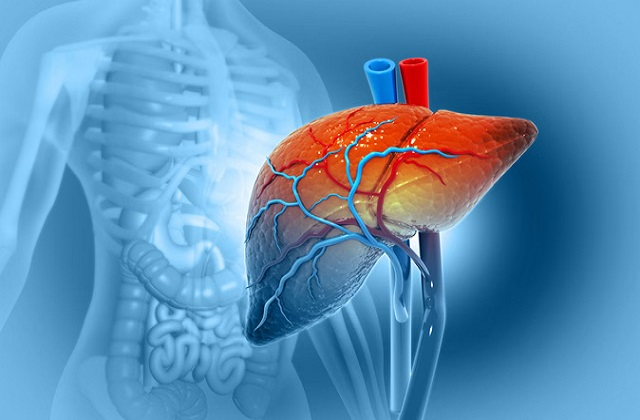

लाइफस्टाइल डेस्क। भारत में Liver diseases तेजी से पैर पसार रही हैं। सबसे डराने वाली बात यह है कि लिवर की बीमारी के लक्षण तब तक सामने नहीं आते, जब तक कि स्थिति बहुत गंभीर न हो जाए। इसलिए लिवर की बीमारियों का जल्दी पता नहीं चल पाता। लेकिन कुछ संकेतों पर ध्यान देकर आप वक्त रहते डॉक्टर की मदद से बीमारी का पता लगा सकते हैं।

थकान अक्सर लिवर खराब होने का पहला संकेत होती है। जब लिवर ठीक से काम नहीं करता, तो ब्लड में टॉक्सिन्स जमा होने लगते हैं। इससे दिमाग की काम करने की क्षमता और शरीर की एनर्जी प्रभावित होती है। जब लिवर बिलीरुबिन को सही ढंग से प्रोसेस नहीं कर पाता, तो यह शरीर में जमा होने लगता है, जिससे त्वचा और आंखों में पीलापन आ जाता है।लोग इसी लक्षण के बाद डॉक्टर के पास जाते हैं, लेकिन तब तक बीमारी काफी बढ़ चुकी होती है।

लिवर खराब होने पर पाचन तंत्र पर सीधा असर पड़ता है। भारत की 9% से 32% आबादी फैटी लिवर से जूझ रही है। आजकल युवाओं में भी भूख न लगने जैसे लक्षण आम होते जा रहे हैं, जो लिवर की समस्या का संकेत हो सकते हैं। पेट में फ्लूएड का जमा होना लिवर के गंभीर रूप से डैमेज होने का संकेत है।

अगर पेशाब का रंग गहरा है और मल का रंग असामान्य रूप से हल्का है, तो यह बाइल के फ्लो में समस्या का संकेत हो सकता है। कई लोग इसे केवल डिहाइड्रेशन समझकर नजरअंदाज कर देते हैं, जो बाद में महंगा पड़ता है। बिना किसी रैशेज या दाने के शरीर पर खुजली होना लिवर की बीमारी का एक छिपा हुआ लक्षण हो सकता है।